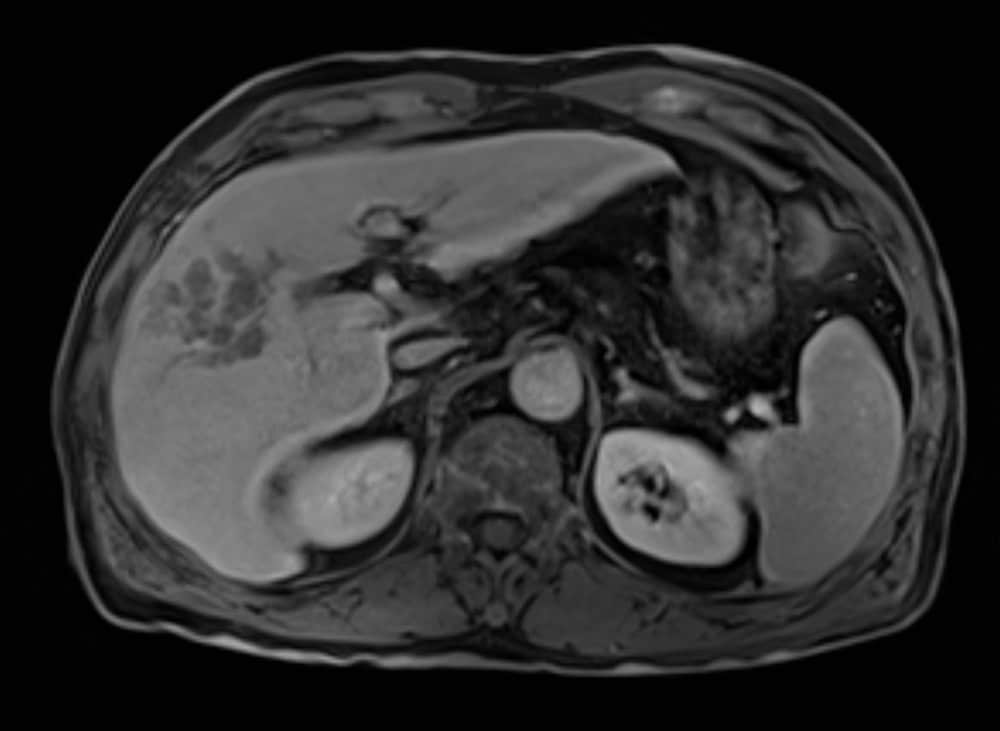

60歳代、男性、57kg、肝細胞癌

前医よりB型慢性肝炎に対して核酸アナログ投与し定期フォローを継続されていた.AFP上昇,腹部USでの画像異常を指摘され精査加療目的に当院紹介受診となり,EOB-MRIを施行した.

EOB-MRIの結果から門脈本幹までの腫瘍栓を伴う肝細胞癌と診断した.EOB-MRI肝細胞相で不均一高信号を呈する病変ではなく,均一低信号を呈しており複合免疫療法が奏効する可能性があると考えられた.Vp4の門脈腫瘍栓を伴う切除不能進行肝癌に対し複合免疫療法(Atezolizumab/Bevacizumab併用療法)を開始した.4コース終了後には門脈腫瘍栓一部残存を認めるも肝腫瘤は著明に縮小し,5コース終了後に根治切除術(肝右葉切除術+門脈血栓除去術)を施行した.術後は薬物療法の再開なく現在までの約14ヶ月無再発で経過観察継続中である.

本症例におけるEOB・プリモビスト造影MRIの役割について

EOB-MRIで門脈腫瘍栓を伴う肝細胞癌であること,不均一高信号を呈する病変で無いことを確認し複合免疫療法(Atezolizumab/Bevacizumab併用療法)を開始した.EOB-MRI肝細胞相は肝細胞癌におけるWnt/βカテニン変異のイメージングバイオマーカーとなることが知られており(Ueno A et al. J Hepatol 61:1080-1087,2014),不均一高信号な病変は複合免疫療法の治療効果が乏しい可能性が指摘されている(Sasaki et al. Cancers,14,827,2022).必ずしも治療奏効を保障するものでは無いが,本症例では肝細胞相で均一低信号を呈しており,複合免疫療法の治療効果が期待される症例であった.